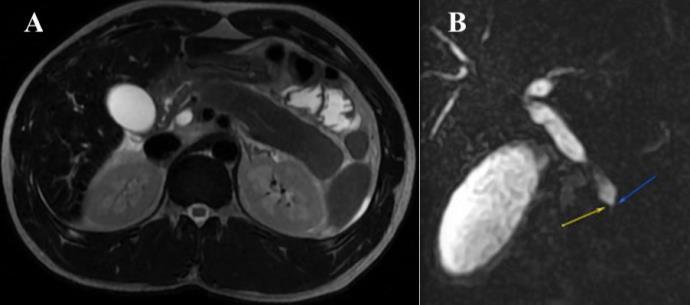

BACKGROUND/INTRODUCTION: The natural progression of interstitial lung disease in patients with dermatomyositis varies significantly. Some patients are asymptomatic or present with slowly progressive symptoms. A small minority of patients, however, present with an amyopathic (muscle-sparing) variant associated with rapidly progressive lung disease. This type of dermatomyositis is associated with the antimelanoma differentiation-associated gene 5 (MDA-5) autoantibody and is nearly uniformly fatal unless acted upon early and aggressively.

CASE PRESENTATION: We describe a case report of a 32-year-old male with no past medical history who presented to the hospital with a 2-month history of worsening dyspnea, cough, fatigue, involuntary weight loss, and myalgia. Prior to this presentation, he attended multiple emergency departments, urgent care, and outpatient visits for these symptoms. Hetested negative for COVID-19multiple times and initially treated for acute bronchitis and later for multifocal pneumonia during those encounters. His workup for pulmonary embolism was negative and computed tomography-chest showed diffuse patchy consolidations with lower lobe predominance. Pulmonary function tests demonstrated a restrictive pattern. The patient underwent extensive infectious and oncologic workup, all unrevealing. An initial myositis panel was negative. At the time of his exam with Rheumatology, a repeat myositis panel and skin biopsy were pending. On physical examination, the patient demonstrated diffuse inspiratory crackles bilaterally on auscultation, subtle violaceous plaques on his knees, and elbows, as well as nose, cheeks, and forehead. He had palmar erythema associated with fissuring and cracking of the skin of the palms, Gottron's papules on his fingers, and pronounced proximal muscular weakness characterized by limited neck flexion. Given the constellation of skin findings, myalgia, lung imaging, and rapidly progressive respiratory failure, a clinical diagnosis of melanoma differentiation-associated gene 5 (MDA5) dermatomyositis was made and later confirmed with a positive MDA5 test on the repeat myositis panel. Subsequently, he was aggressively treated with intravenous methylprednisolone, intravenous immunoglobulin (IVIG), and combination cyclophosphamide/tacrolimus therapy

CONCLUSION: Interstitial lung disease occurs in at least 30 percent of patients diagnosed with dermatomyositis. The presence of melanoma differentiation-associated gene 5 antibodies is linked to the elevated risk for interstitial lung disease progression, and for this reason, early recognition of cutaneous findings in the setting of myalgias and respiratory failure is crucial for early intervention and aggressive systemic treatment. This case report represents the importance of the physical examination for early diagnosis and management particularly relevant in the absence of available specific autoantibody tests.

34

ABSTRACT #11

CASE REPORT/CLINICAL REVIEW/CLINICAL VIGNETTE INFECTIOUS DISEASES

ELSBERG SYNDROME IN HSV-2 INFECTION

Omar Belfaqeeh1, Alexandria Markley1, Mudita Patel1,2, Brian Markoff1, Georgina Osorio1

1Mount Sinai Morningside-West Hospitals, Icahn School of Medicine at Mount Sinai, New York, NY, United States;

2Mount Sinai Beth Israel Hospital, Icahn School of Medicine at Mount Sinai, New York, NY, United States

Published in IDCases, 2023. PMID: 36875152

BACKGROUND/INTRODUCTION: Elsberg syndrome is a neuroinflammatory disease that causes acute or subacute lumbosacral radiculitis, with or without myelitis. Elsberg syndrome typically presents as cauda equina syndrome, with symptoms of sensory impairment, lower extremity weakness, saddle anesthesia, and urinary and/or bowel incontinence. It is usually associated with infectious causes such as SARS-CoV-2, West Nile Virus, Varicella Zoster Virus (VZV), and Herpes Simplex Virus Type 2 (HSV-2), with HSV-2 being the predominate causative pathogen. Treatment with acyclovir, even in cases without a definitive viral cause, is considered beneficial in many cases. Duration of treatment varies and is typically between 10 and 21 days. The use of steroids in the treatment of Elsberg syndrome is debated. Oral steroid tapers or short course high dose intravenous steroids can be used to help shorten the duration of symptoms. Elsberg syndrome accounts for approximately 5–10% of cauda equina syndrome and myelitis and up to 30% of patients have a recurrence of symptoms within the first year. Below we present a unique case of HSV-2 lumbosacral radiculitis (Elsberg Syndrome) diagnosed at a large New York City Hospital Center.

CASE PRESENTATION: Our patient was a 51-year-old female with a past medical history significant for fibromyalgia, right-sided sciatica, right lower extremity deep venous thrombosis, asthma, nephrolithiasis, vertigo, and oral and genital herpes infection who recently returned from Dominican Republic. She presented to the emergency room with complaints of a 10-day history of progressive lower extremity sensory changes and weakness preceded by transient bilateral arm pain and neck and head pressure. Furthermore, she reported being unable to completely void for one day in duration. She described the weakness to be worse in the right leg compared to the left leg, describing it as “leg heaviness” which resulted in a fall at home a day prior to presentation. While she was sitting in the bathroom, she tried to stand but her knees ’buckled’ and she fell backward, hitting her head on the floor (denied any loss of consciousness). Her family carried her to the Emergency Department as she was unable to bear weight. Vital signs on presentation were within normal limits. Physical exam was most notable for reduced power of knee flexors and knee extensors (3/5), dysesthesia to touch and pinprick from mid-thigh distally in stocking distribution bilaterally, absent knee reflexes bilaterally, positive Babinski sign bilaterally, and no clonus. Given her weakness and urinary hesitancy, a magnetic resonance imaging (MRI) of the cervical, thoracic, and lumbar spine was done to assess for spinal cord pathology and a bladder scan was done to rule out urinary retention. Neurology evaluated the patient for acute progressive lower extremity neuropathic pain and weakness. A lumbar puncture was performed to rule out atypical Guillain Barre syndrome or multiple sclerosis.

Complete blood count showed a white blood cell count of 5.1 ×103 cells/mL, hemoglobin of 11.9 g/dL, platelet count of 371 × 103 cells/ mL, and eosinophils elevated to 5.7%. The basic metabolic panel was within normal limits. Vitamin B12 level came back low at 290 pg/mL, homocysteine of 11.2, erythrocyte sedimentation rate of 30.9 and c-reactive protein of 5.9. Other labs including creatine phosphokinase, aldolase, methylmalonic acid, Lyme titers, copper level, vitamin B12, SSA/SSB (Sjogren Antibodies), were unremarkable. The cerebrospinal fluid PCR cytology showed pleocytosis with a WBC count of 360 (100% lymphocytes), although no albumin cytologic dissociation was seen, and protein of 182 mg/dL. Cerebrospinal fluid PCR was positive for HSV-2.

Infectious disease was consulted and reviewed the MRI of the spine with radiology, which demonstrated a very faint enhancement of the L4–5 nerve roots. An MRI of the brain came back within normal limits. An initial

35